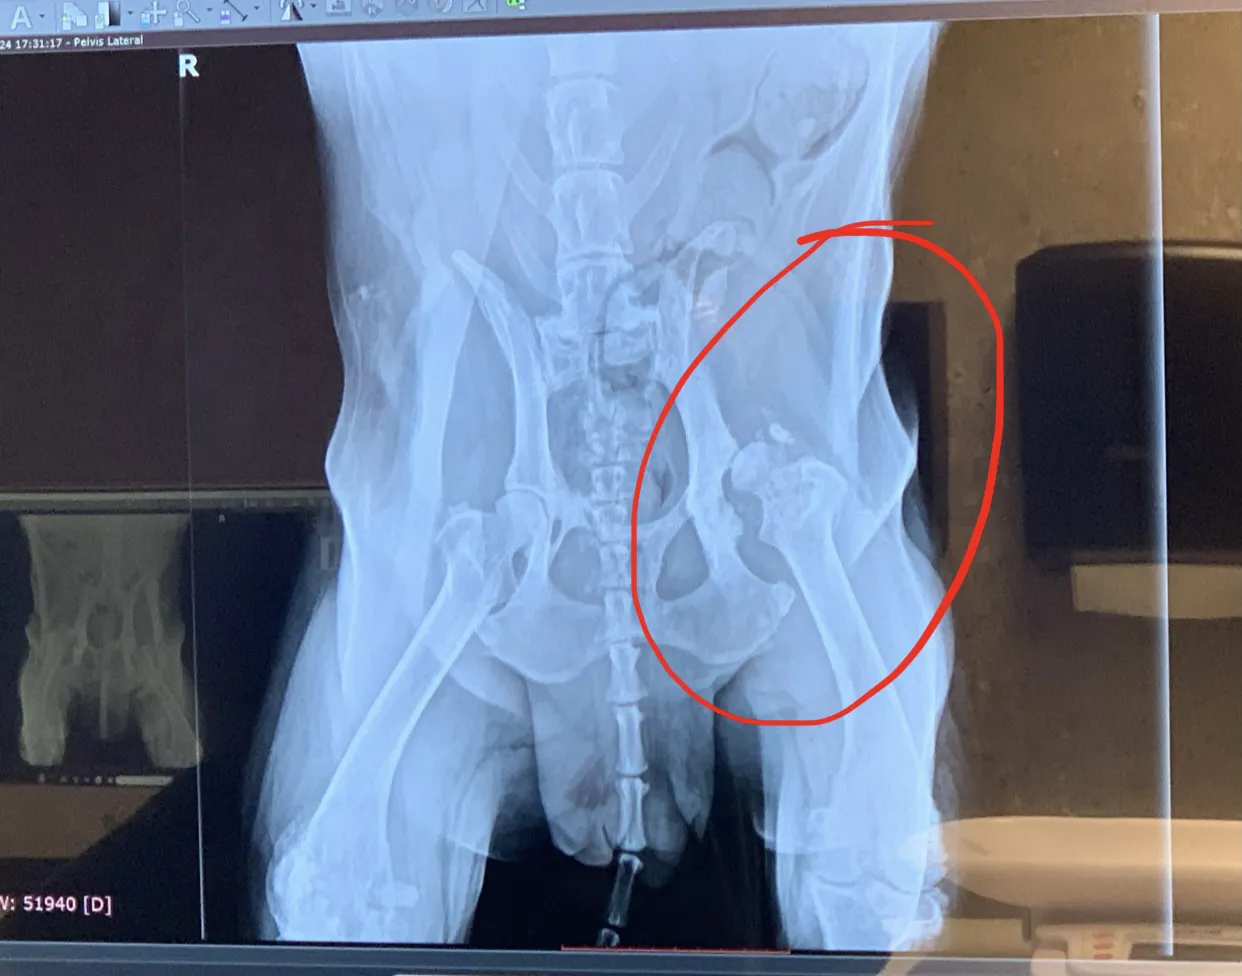

A ello se suma el hecho de que hace apenas un més, la perrita sufrió una caída que le afectó seriamente al fémur de la pata trasera izquierda desplazándolo de la cavidad en la que va encajado en la cadera.

Ahora, a esa lesión y a todas las patologías que tuvo es apenas 2 años, hay que sumar esta nueva recaída que es motivada, según el servicio veterinario que la atiende, por un nuevo proceso infeccioso que le ha llenado de líquidos las articulaciones haciendo que sea imposible que se pueda mantener en pie.